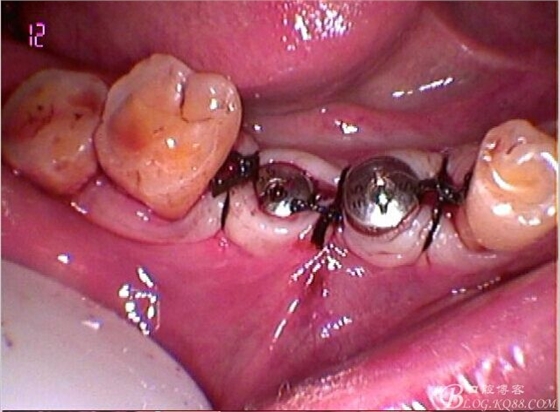

因為左上做過種植,口內(nèi)見

C6頰側(cè)骨缺損凹陷,對合金屬全冠,

一月復(fù)查,上皮袖口封閉良好,牙齦恢復(fù)正常外形凸度,但近中齦乳頭仍不理想

試戴個性化基臺,牙齦外形穩(wěn)定

牙齦封閉良好,咬合,近中觸點穩(wěn)定